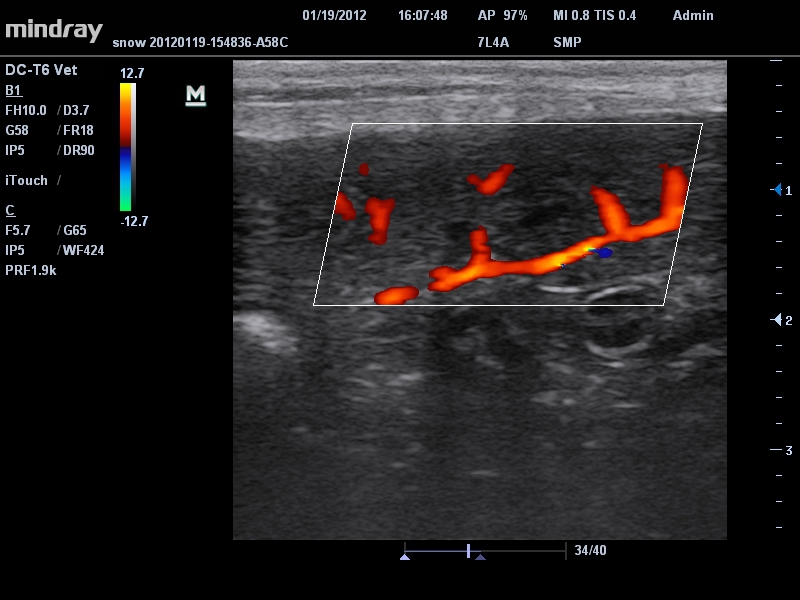

• Линейный ультразвуковой датчик Mindray 7L4A

• Режимы сканирования: B/M/CFM/PDI/Направленный PDI/PW, HPRF, Тканевая гармоника, М- и цветной М-режим.

Энергетический допплер:

Да